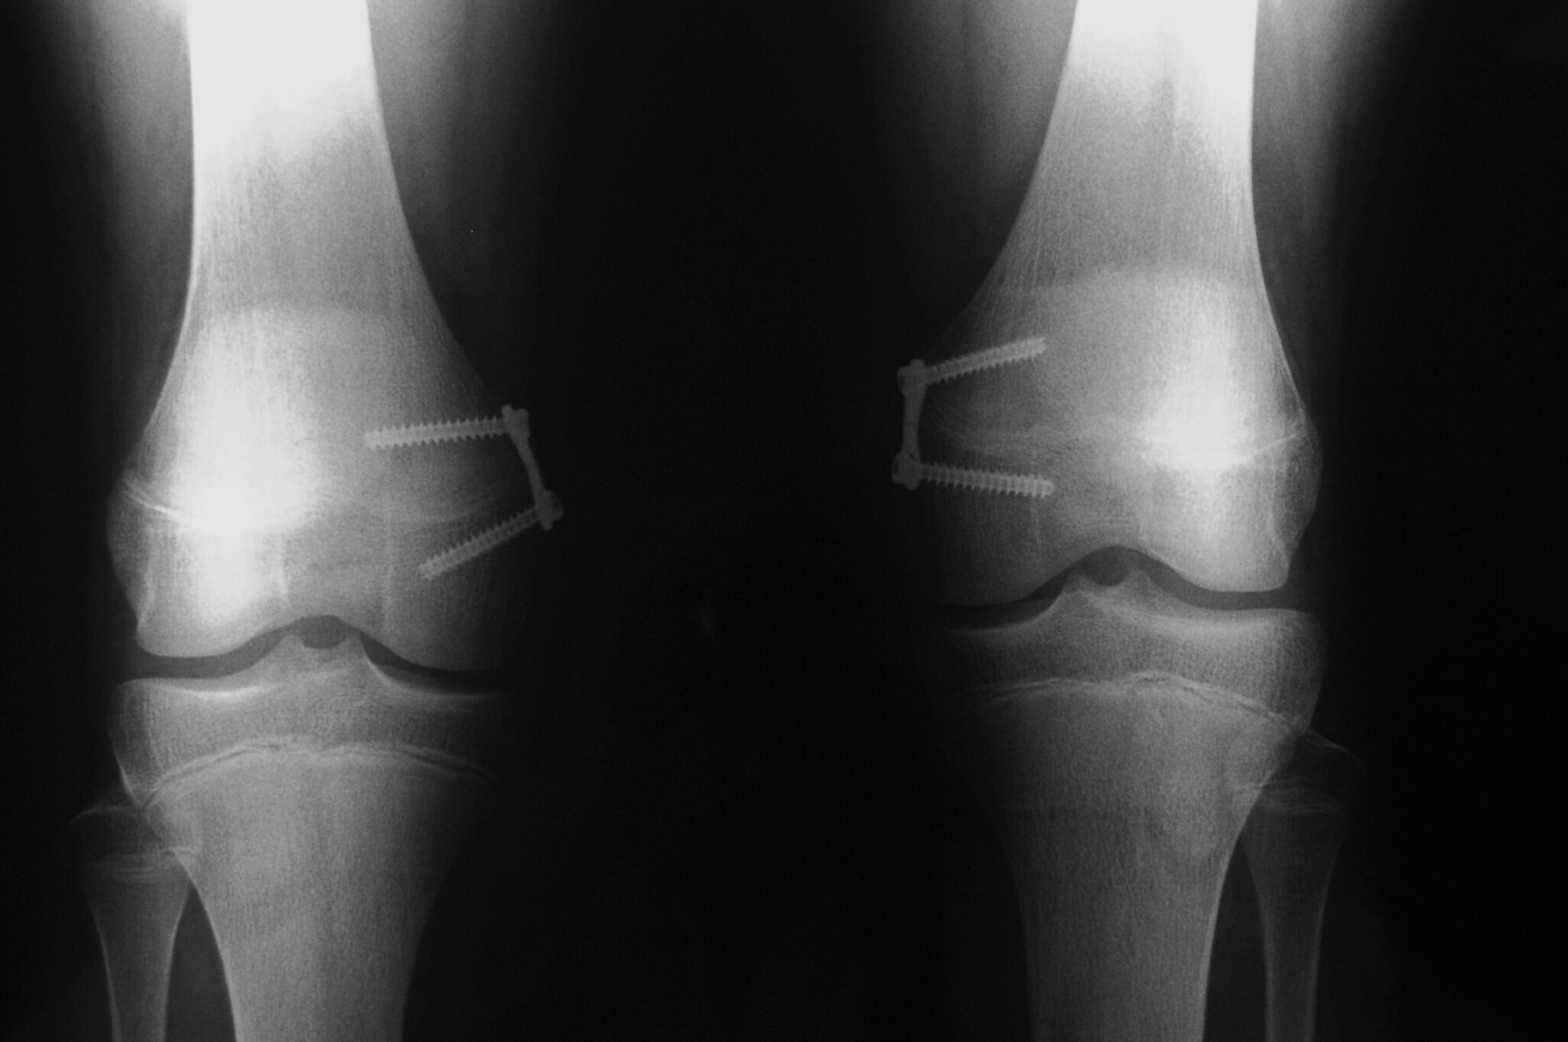

Una vez realizada la evaluación clínica, el siguiente paso es obtener imágenes detalladas de las rodillas y las piernas para observar con precisión la alineación ósea. Las radiografías son la herramienta más comúnmente utilizada para este fin y permiten medir el ángulo de alineación de las rodillas. El ángulo varía dependiendo de la gravedad del genu valgo, y se puede calcular midiendo la distancia entre las líneas que forman los ejes del fémur y la tibia. Este ángulo se conoce como el ángulo de la deformidad en «X».

Las radiografías permiten clasificar la severidad del genu valgo y proporcionan detalles cruciales sobre la relación entre la tibia y el fémur, que ayuda a planificar el tratamiento adecuado. También se pueden identificar otras condiciones asociadas, como lesiones en los huesos o cartílago, o patologías articulares como la osteoartritis, que podrían estar contribuyendo a la deformidad.

Radiografía Genu Valgo

La osteotomía es una intervención quirúrgica que implica cortar y realinear los huesos de las piernas, generalmente el fémur o la tibia. En esta cirugía, se reposiciona el hueso para corregir la alineación de la rodilla y aliviar el dolor. La osteotomía puede ser útil en personas jóvenes y activas que desean evitar una cirugía de reemplazo de rodilla.